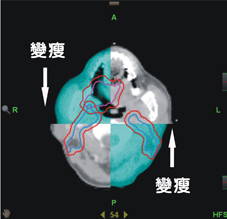

另外在影像導影系統下,我們發現每日位移量最多可達1cm,仍然超出傳統強度調控放射線治療計畫之添加距離範圍(如:圖三)。故導航螺旋刀治療患者,透過每日影像導影系統進行每日治療位置之校正,截至目前案例,並無邊緣治療失敗之個案。反觀傳統強度調控放射線治療,其邊緣治療失敗占了失敗案例中的52%,此邊緣治療失敗的原因對於傳統強度調控放射線治療較差的局部控制與較差的存活率上,亦造成一定程度之影響。

圖三、影像導引系統可提前發現病人體態變化而做出修正